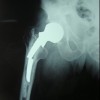

Surgical debridement of the septic left SCJ under general anesthesia was performed. Exposure was made through a linear incision of about 11 cm in length, starting over the medial aspect of the clavicle and extending over the sternal body, over the anterior region of the left SCJ. Fistulectomy, drainage of the abscess and thorough irrigation were undertaken. Resection of the intra-articular disc, debridement of all devitalized tissue and curettage of both the clavicle head and lateral sternal body to healthy bone were performed. At the end of the procedure, the residual bone defect was measured approximately 1 cm in width and 1 cm in depth (Fig. 3). Resected tissue cultures were positive for MRSA. Postoperatively, antibacterial therapy with intravenous linezolid (600 mg every 12 h) was administered for 14 days and was continued orally with levofloxacin (500 mg every 12 h) for 12 weeks, due to linezolid-induced myelosuppression.

The surgical wounds healed completely. 2 weeks postoperatively, the patient was pain-free with full active range of motion of the shoulder (Fig. 4). CT scan performed at 6-month follow-up showed no signs of recurrent infection (Fig. 5). At 18-months follow-up, the patient maintained a full range of motion with symmetrical strength in his left upper limb with no pain or tenderness in the surgical site (Fig. 6).